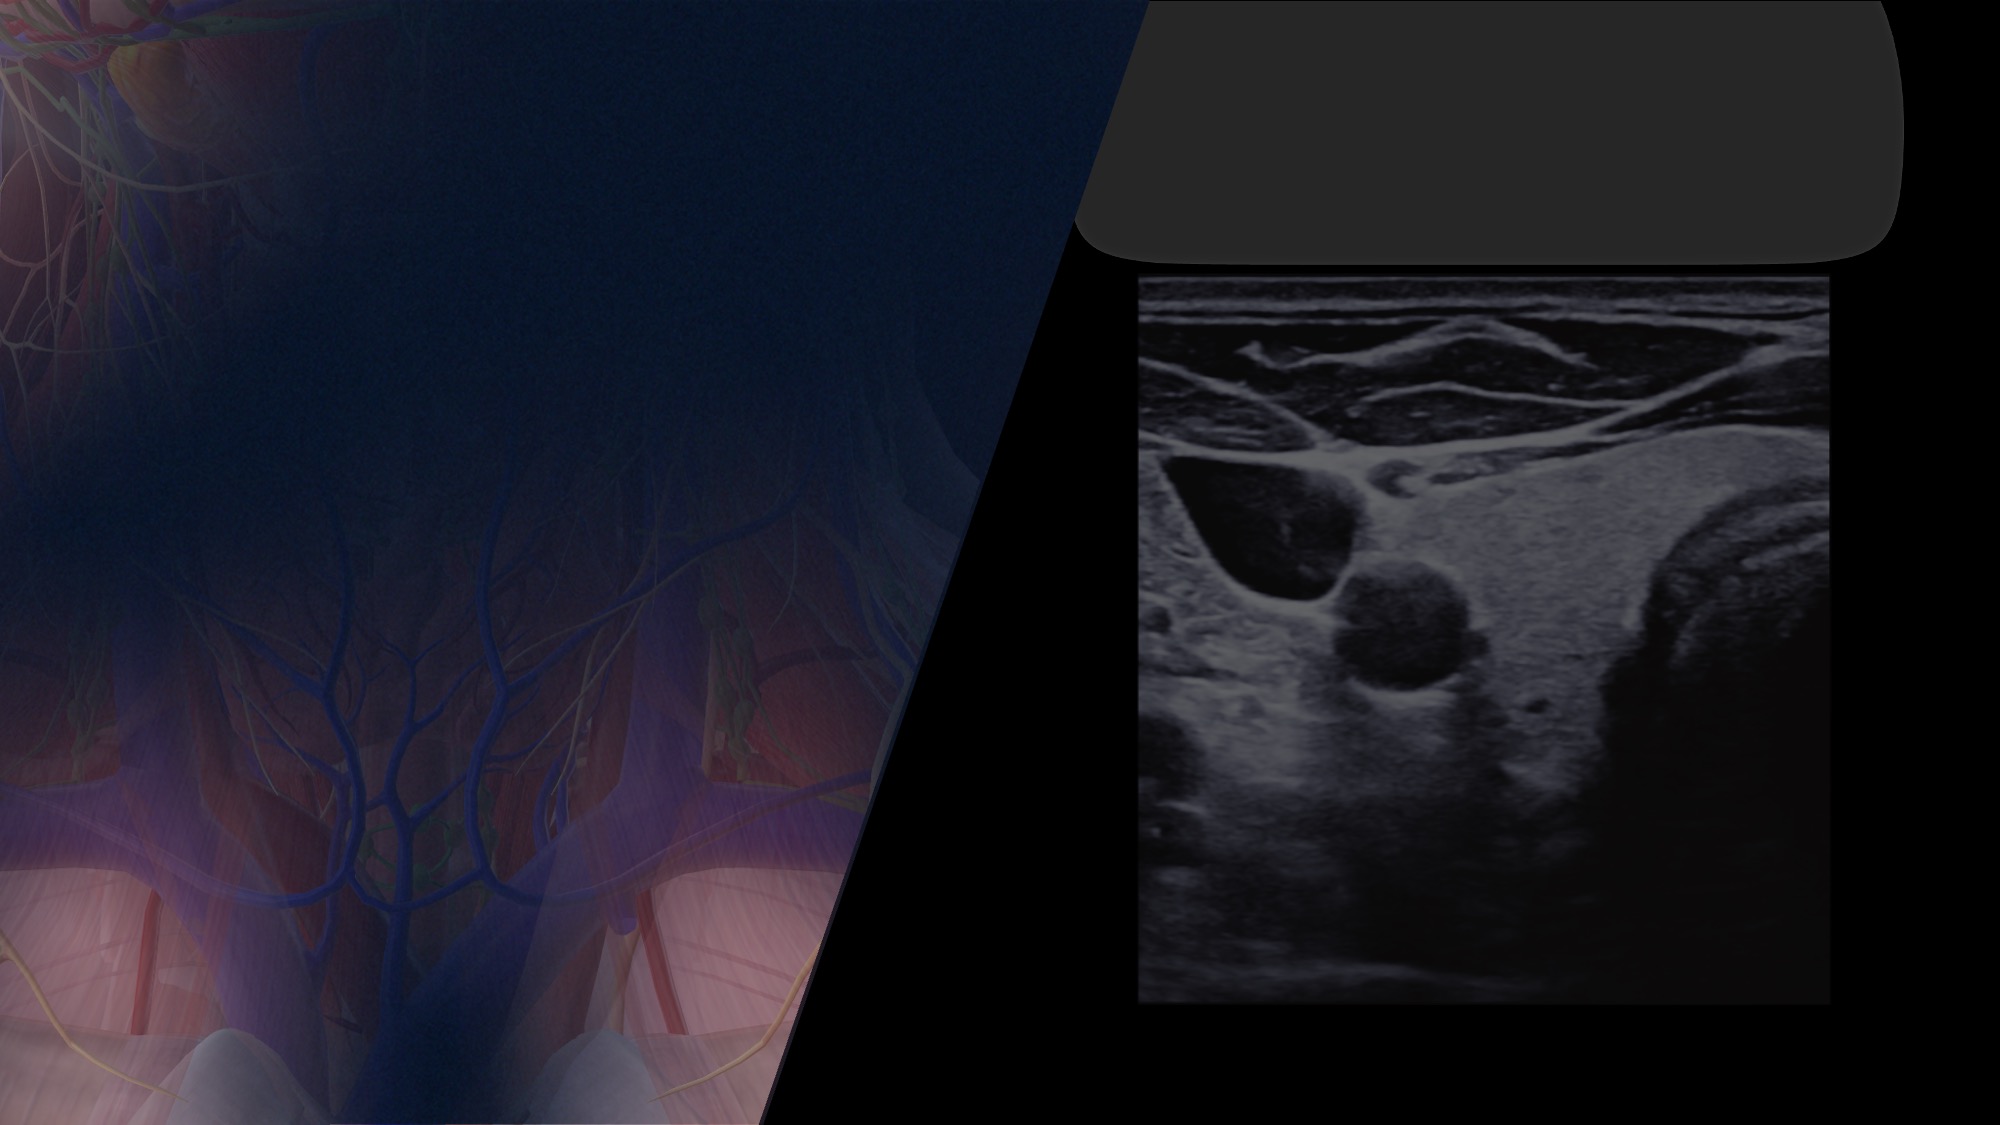

Anatomie osseuse pour l'échographie de la thyroïde Ce contenu est gratuit Ce contenu est réservé aux professionnels de santé Identifiez-vous pour pouvoir y accéder. « * » indique les champs nécessaires Nom* Prénom Nom E-mail* Département*Pays*FranceBelgique-----------AfghanistanAfrique du SudAlbanieAlgérieAllemagneAndorreAngolaAnguillaAntarctiqueAntigua-et-BarbudaArabie SaouditeArgentineArménieArubaAustralieAutricheAzerbaïdjanBahamasBahreïnBangladeshBelarusBelizeBermudesBhoutanBolivieBonaire, Saint-Eustache et SabaBosnie-HerzégovineBotswanaBrunei DarussalamBrésilBulgarieBurkina FasoBurundiBéninCambodgeCamerounCanadaCap-VertChiliChineChypreColombieComoresCongoCorée (République de)Corée (République populaire démocratique de)Costa RicaCroatieCubaCuraçaoCôte d’IvoireDanemarkDjiboutiDominiqueEspagneEstonieEswatiniFidjiFinlandeFédération RusseGabonGambieGhanaGibraltarGrenadeGroenlandGrèceGuadeloupeGuamGuatemalaGuernseyGuinéeGuinée équatorialeGuinée-BissauGuyaneGuyaneGéorgieGéorgie du Sud et Îles Sandwich du SudHaïtiHondurasHong KongHongrieIndeIndonésieIrakIranIrlandeIslandeIsraëlItalieJamaïqueJaponJerseyJordanieKazakhstanKenyaKirghizistanKiribatiKoweïtLa BarbadeLa RéunionLesothoLettonieLibanLiberiaLibyeLiechtensteinLituanieLuxembourgMacaoMacédoine du NordMadagascarMalaisieMalawiMaldivesMaliMalteMarocMartiniqueMauritanieMayotteMexiqueMicronésieMoldavieMonacoMongolieMontserratMonténégroMozambiqueMyanmarNamibieNauruNicaraguaNigerNigériaNiuéNorvègeNouvelle-CalédonieNouvelle-ZélandeNépalOmanOugandaOuzbékistanPakistanPalauPanamaPapouasie-Nouvelle-GuinéeParaguayPays-BasPhilippinesPolognePolynésie françaisePorto RicoPortugalPérouQatarRoumanieRoyaume-UniRwandaRépublique DominicaineRépublique TchèqueRépublique arabe syrienneRépublique centrafricaineRépublique démocratique du CongoRépublique démocratique populaire du LaosSahara occidentalSaint BarthélemySaint MartinSaint Pierre et MiquelonSaint-Christophe-et-NevisSaint-MarinSaint-SiègeSaint-Vincent-et-les GrenadinesSainte-Hélène, Ascension et Tristan da CunhaSainte-LucieSalvadorSamoaSamoa américainesSao Tomé et PrincipeSerbieSeychellesSierra LeoneSingapourSint MaartenSlovaquieSlovénieSomalieSoudanSoudan du SudSri LankaSuisseSurinameSuèdeSénégalTadjikistanTanzanie (République-Unie de)TaïwanTchadTerres Australes FrançaisesTerritoire britannique de l’océan IndienThaïlandeTimor orientalTogoTokelauTongaTrinité et TobagoTunisieTurkménistanTurquieTuvaluUkraineUruguayVanuatuVenezuelaVietnamWallis et FutunaYémenZambieZimbabweÉgypteÉmirats arabes unisÉquateurÉrythréeÉtat palestinienÉtats-UnisÉthiopieÎle BouvetÎle ChristmasÎle MauriceÎle NorfolkÎle de ManÎles CaymanÎles CocosÎles CookÎles FalklandÎles FéroéÎles Heard et McDonaldÎles Mariannes du NordÎles MarshallÎles PitcairnÎles SalomonÎles Turques et CaïquesÎles Vierges américainesÎles Vierges britanniquesÎles de Svalbard et Jan MayenÎles mineures américainesÎles Åland Formation 7 : Échographie de la thyroïde niveau 1 Module 2 chap 1 : Anatomie osseuse Module 2Repères anatomiques Chapitre 1 : Anatomie osseuse Chapitre 2 : Anatomie vasculaire Chapitre 3 : Anatomie musculaire Module précédent Chap. suivant Notre gamme d'échographes Samsung Demandez un essai En savoir plus Échographe Samsung V7 OB/Gyn Demandez un essai En savoir plus Échographe Samsung V8 Demandez un essai En savoir plus Echographe portable Samsung HM70 EVO Demandez un essai En savoir plus Echographe Samsung HS40 Demandez un essai En savoir plus